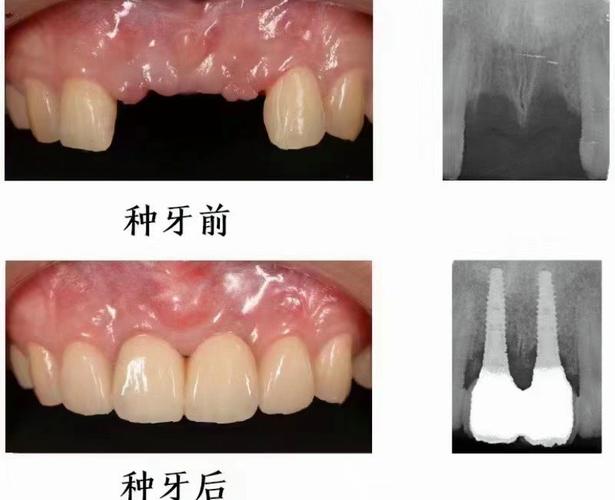

- 医生经验与技术: 种植牙的核心在于医生! 了解主诊医生的种植经验(从业年限、种植数量)、技术风格、是否接受过系统培训、擅长哪些种植系统(如ITI、Nobel、Osstem、Dentium等)和种植技术(即刻种植、微创种植、All-on-4/6等),要求查看医生的资质证明和成功案例。

- 设备与材料: 是否配备先进的设备,如口腔CBCT(锥形束CT)、数字化口内扫描仪、种植手术导板等?使用的种植体品牌、基台、牙冠材料是什么?不同品牌和材料价格差异大,质量和长期效果也不同,常见的进口品牌有瑞士Straumann(ITI)、瑞典Nobel Biocare、德国Ankylos、美国Zimmer、韩国Osstem/Dentium等;国产品牌也在快速发展。

- 拍片检查是必须: 没有CBCT等影像学检查,医生无法准确评估您的骨条件,无法制定科学安全的种植方案。